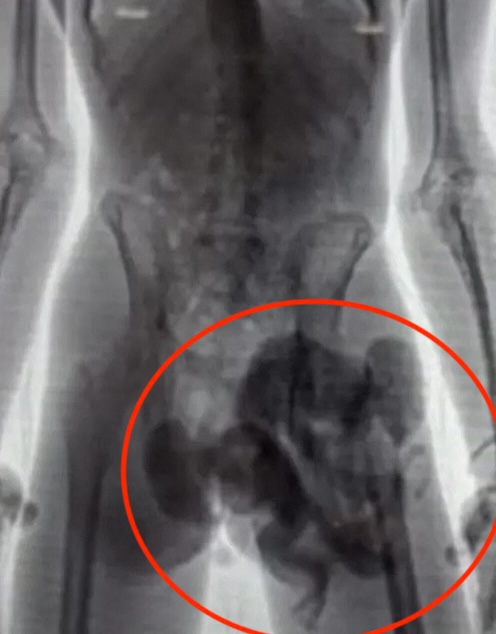

Neznana moški in ženska sta na drugem največjem kolumbijskem letališču v Medellinu poskušala iz države v spodnjem perilu pretihotapiti šest opičjih mladičev. Male živali so uspavali s pomirjevali, jih zavili v platnene vreče in jih stlačili v spodnjice tihotapcev.

Pri tem okrutnem početju so jih ustavili letališki cariniki.

Veterinarski pregled je pokazal, da opičji mladiči niso starejši od dveh mesecev in da so podhranjeni, dehidrirani ter da kažejo znake mučenja. Na žalost sta dve od šestih opic poginili, ostale štiri pa so v veterinarski oskrbi.